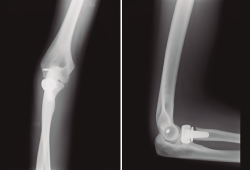

- Fx conminuta de la cabeza de radio Mason IV (no sintetizable), tratada con prótesis de la cabeza de radio ASCENSION® Medcom Tech 22S/cuello corto (Figura 2).

- Fx coronoides conminuta, reinserción con anclaje óseo (Figura 2).

- Reinserción del ligamento lateral externo (LLE) del codo.

- Colocación de férula de yeso a 90°.

Figura 2. Control radiográfico el 31/10/2017.